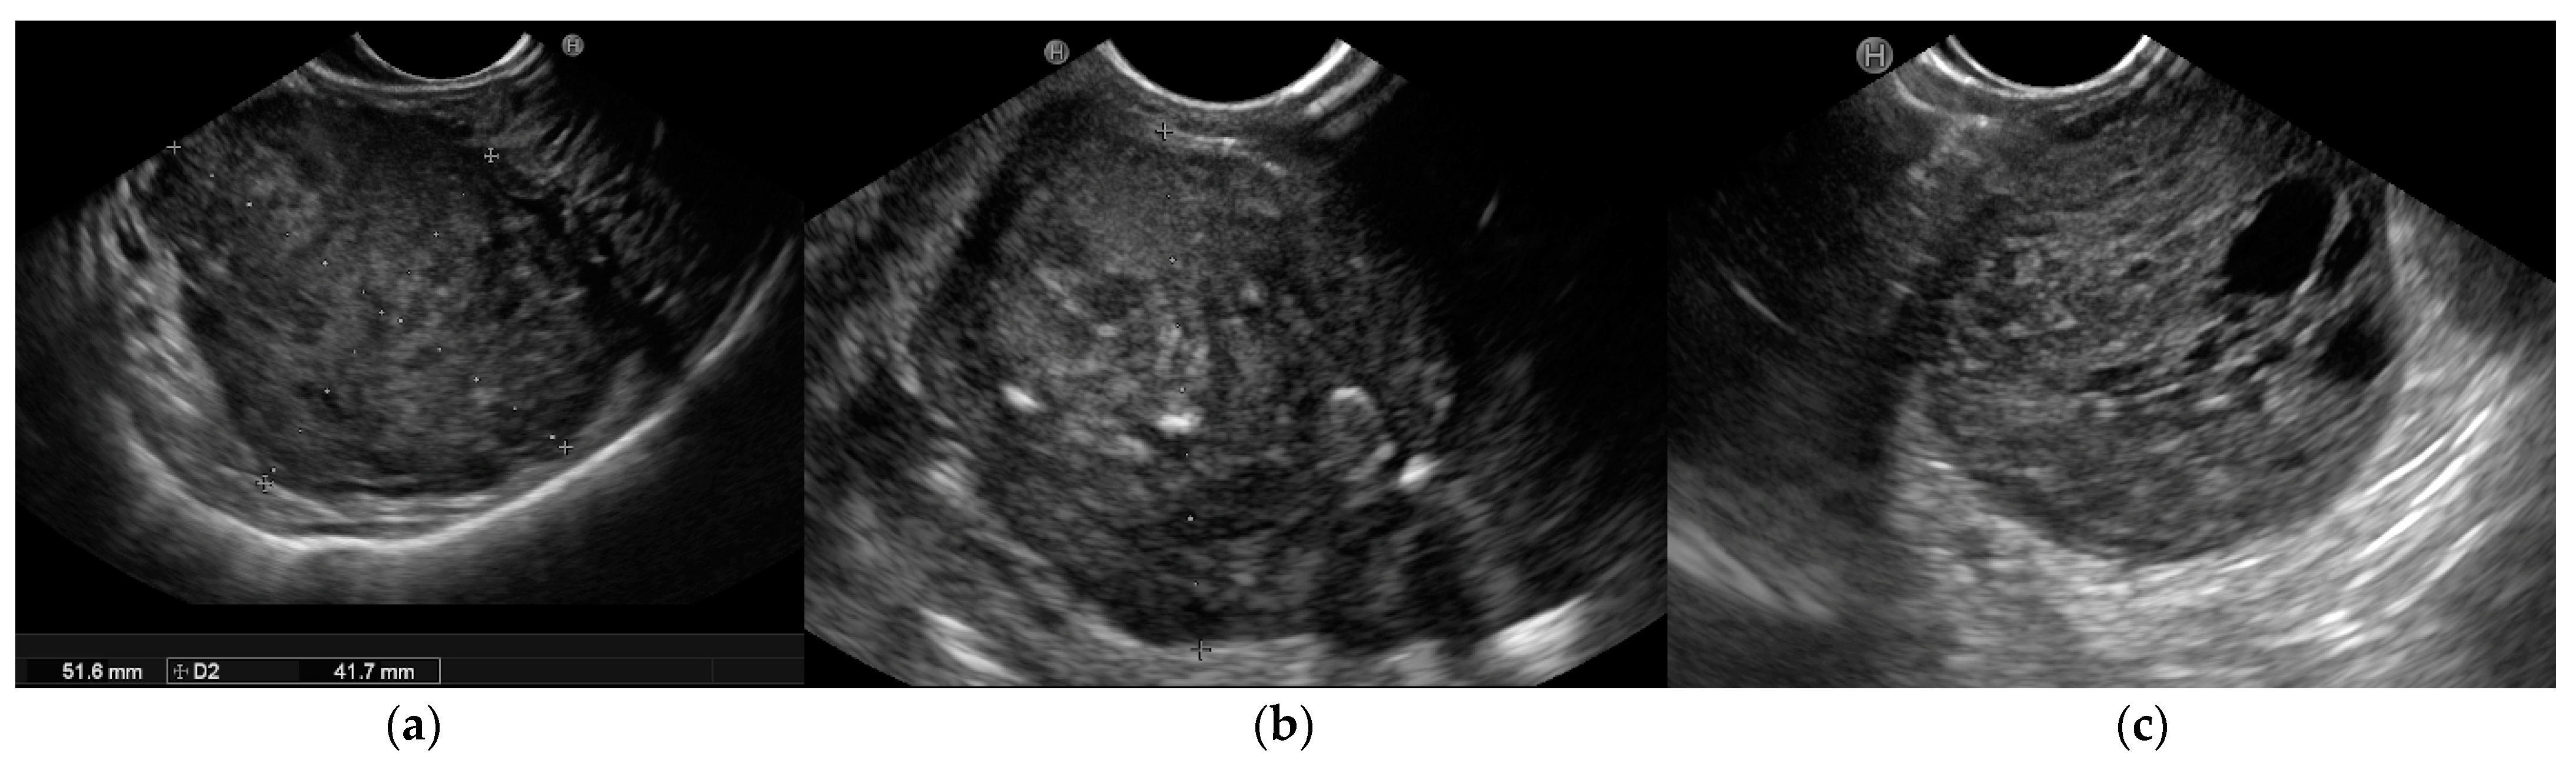

| GIST low risk | 2nd/4th | Hypoechoic, homogeneus, hypervascular. | <30 | Regular | Esophagus, Stomach, Small Intestine, Rectum |

| GIST high risk | 2nd/4th | Hypoecoic, heterogeneus cystic space, echogenic foci, calcifications, dimpling or ulcers. | >30 | Irregular | Esophagus, Stomach, Small Intestine, Rectum |